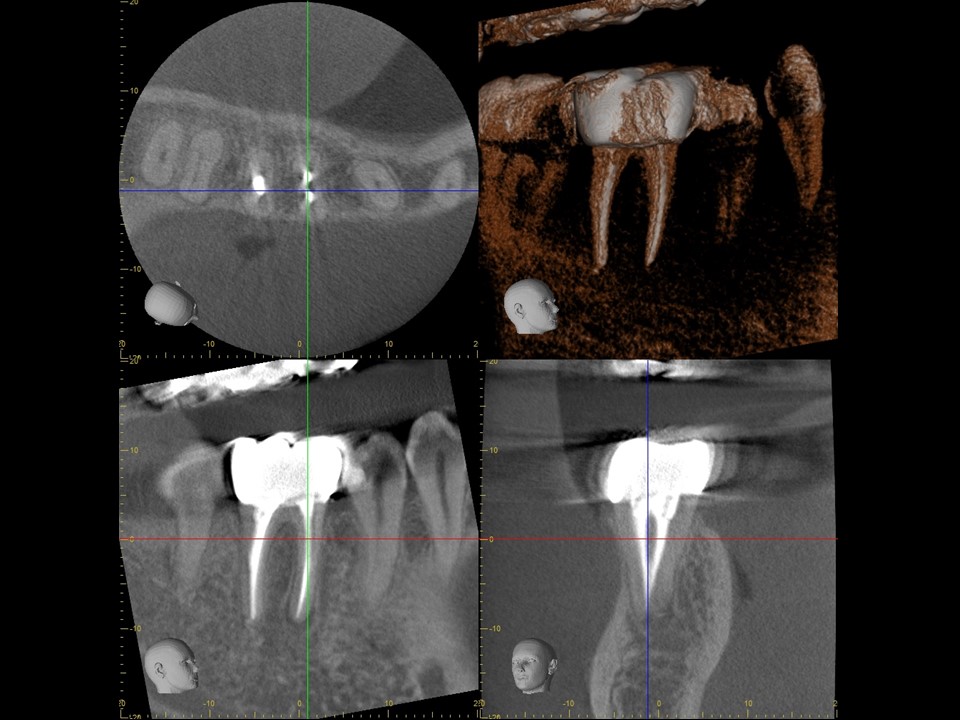

| 治療前レントゲン | 治療前CT |

|---|---|

| 治療前レントゲン |

|---|

| 治療前CT |

初診時レントゲンおよびCT画像です。すでに根管治療はされているが、根尖まで薬が入っておらず、根尖病変と思われる黒い透過像を認めます(矢印)